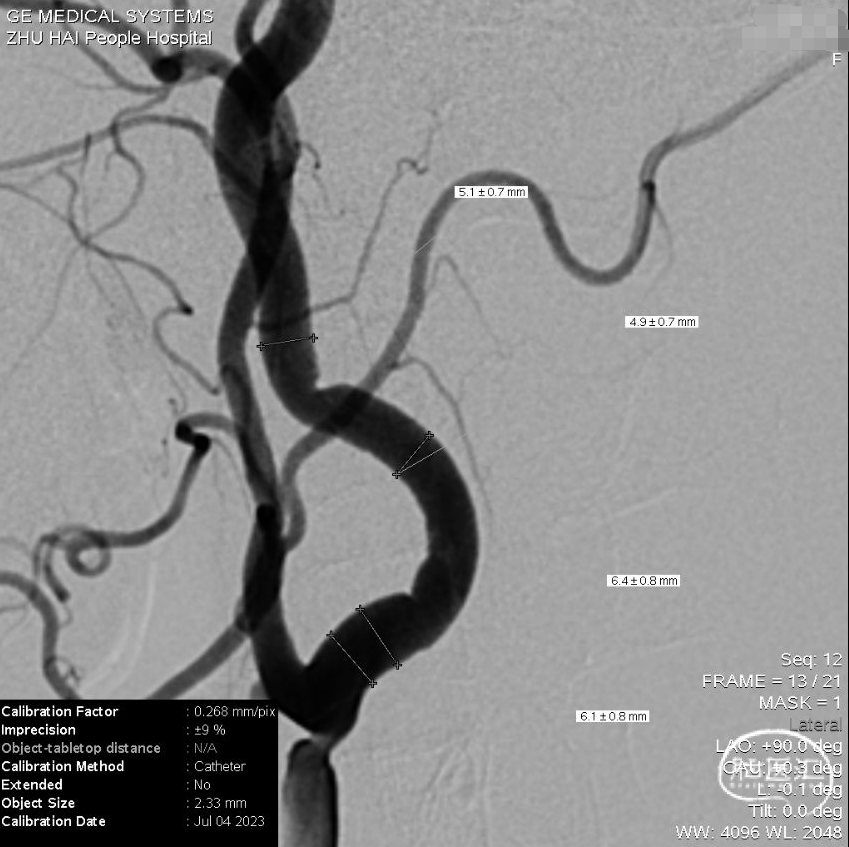

女,59岁,因“发现颈动脉狭窄1周”入院。既往鼻咽癌放疗病史;查体:无异常。

尝试直接推RAC导管,退内衬,造影及测量

造影测量